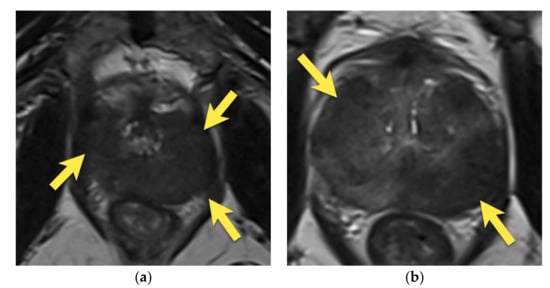

8. Post-Biopsy Hemorrhage